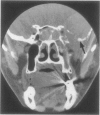

The authors present an unusual case of solitary intramedullary plasmacytoma. Awareness of this entity can facilitate appropriate surgical planning, which may include a limited biopsy prior to considering more extensive skull base surgery.